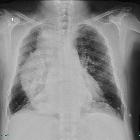

Plain radiograph

Chest radiograph findings include:

- convex opacity overlapping the right mediastinum. Occasionally may present as a left convex opacity if the thoracic aorta is tortuous.

- air-fluid level due to stasis in a thoracic esophagus filled with retained secretions and food

- small or absent gastric bubble

- anterior displacement and bowing of the trachea on the lateral view

- patchy alveolar opacities, usually bilateral, may be seen. These represent acute pneumonitis or chronic aspiration pneumonia related to dysphagia.